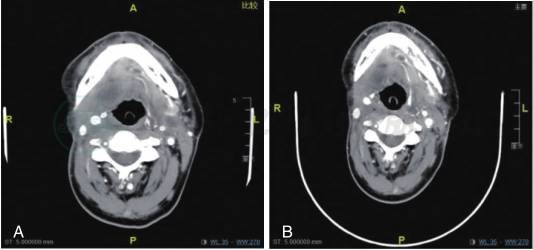

右舌根鳞状细胞癌术后放疗后复发病例的全程管理

1小时条评论59岁男性,右舌根鳞状细胞癌术后放疗后3个月复发。本病例将介绍复发转移性头颈部鳞癌全程管理。 【病例介绍】 患者,男性,59岁。 主诉:右舌根鳞状细胞癌术后放疗后3个月复发。 2018-06-10因右舌根肿物于当地医院切取活检,病理示:鳞状细胞癌。 ...